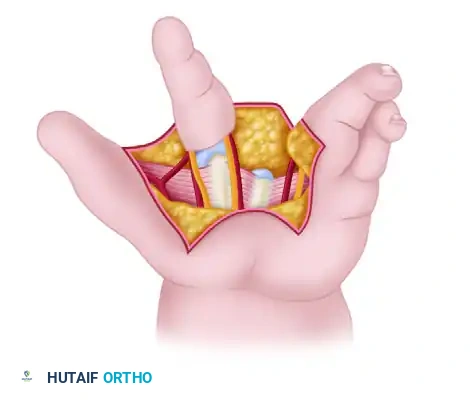

Techniques for Cleft Closure and Web Space Deepening

Closing the cleft requires careful management of the metacarpals. Bony elements that block closure should be excised sparingly; excessive removal of the central metacarpal base can weaken the transverse carpal arch and lead to recurrent clefting.

When cleft closure is combined with first web space deepening, the index ray is often transposed ulnarly to the long metacarpal position.

* Snow and Littler Technique: Involves a complex palmar flap to reconstruct the first web space while transposing the index ray.

* Miura and Komada Technique: A technically less demanding alternative that produces comparable functional results with a significantly lower risk of flap necrosis.

* Upton and Taghinia Technique: Advocates for avoiding complicated dorsal and volar flaps entirely due to the high risk of tip necrosis. Instead, they utilize a simple incision separating the glabrous from the dorsal skin surfaces.

Upton and Taghinia technique: Incisions within the cleft are placed precisely at the juncture of the glabrous and dorsal skin. A small trap-door flap is utilized for commissure lining between the ring and transposed index finger, ensuring robust vascularity.